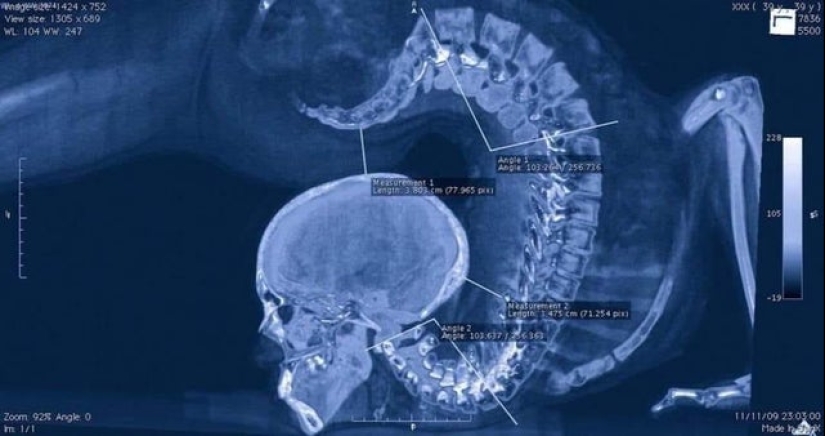

X-ray de gimnastas que hace ejercicios de piso.